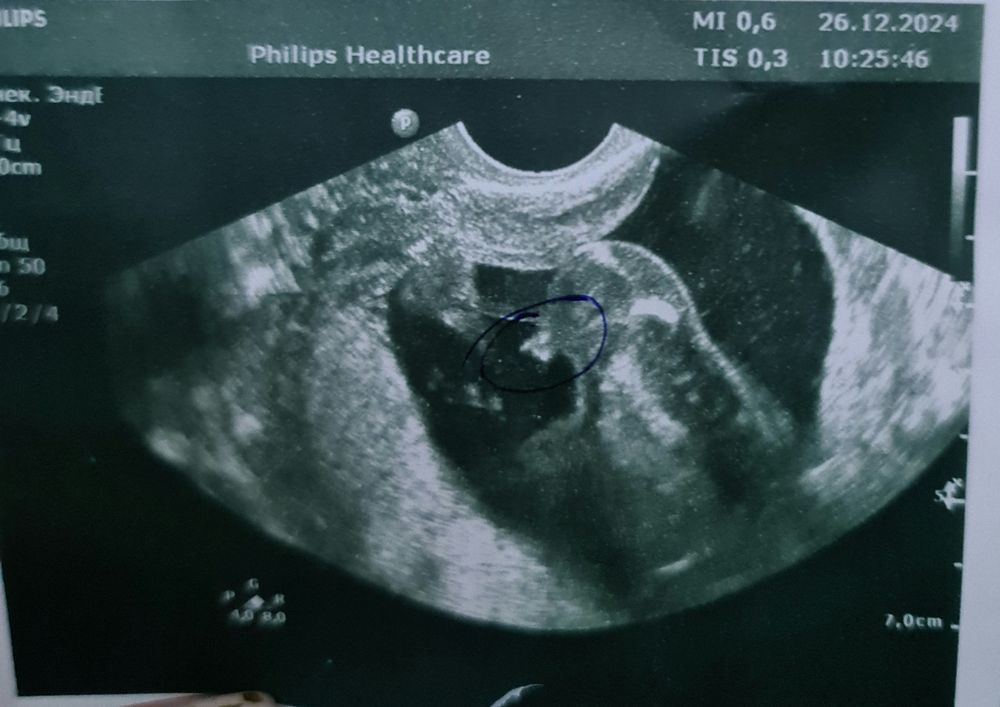

УЗИ, КТГ, доплерПосмотри пожалуйста мальчик, есть такой нюанс что у нас пуповина между ног была, у меня 17 недель.

Посмотри пожалуйста мальчик, есть такой нюанс что у нас пуповина между ног была, у меня 17 недель.